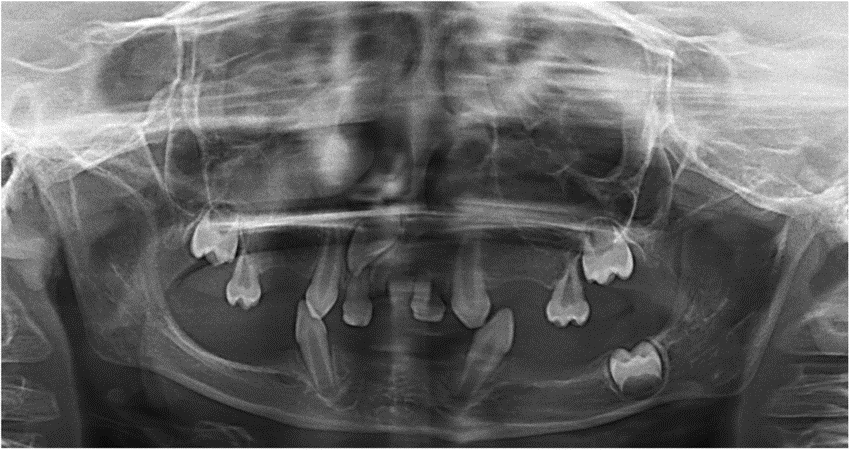

1. (Select ONE OR MORE correct answers)

The radiograph shows evidence of